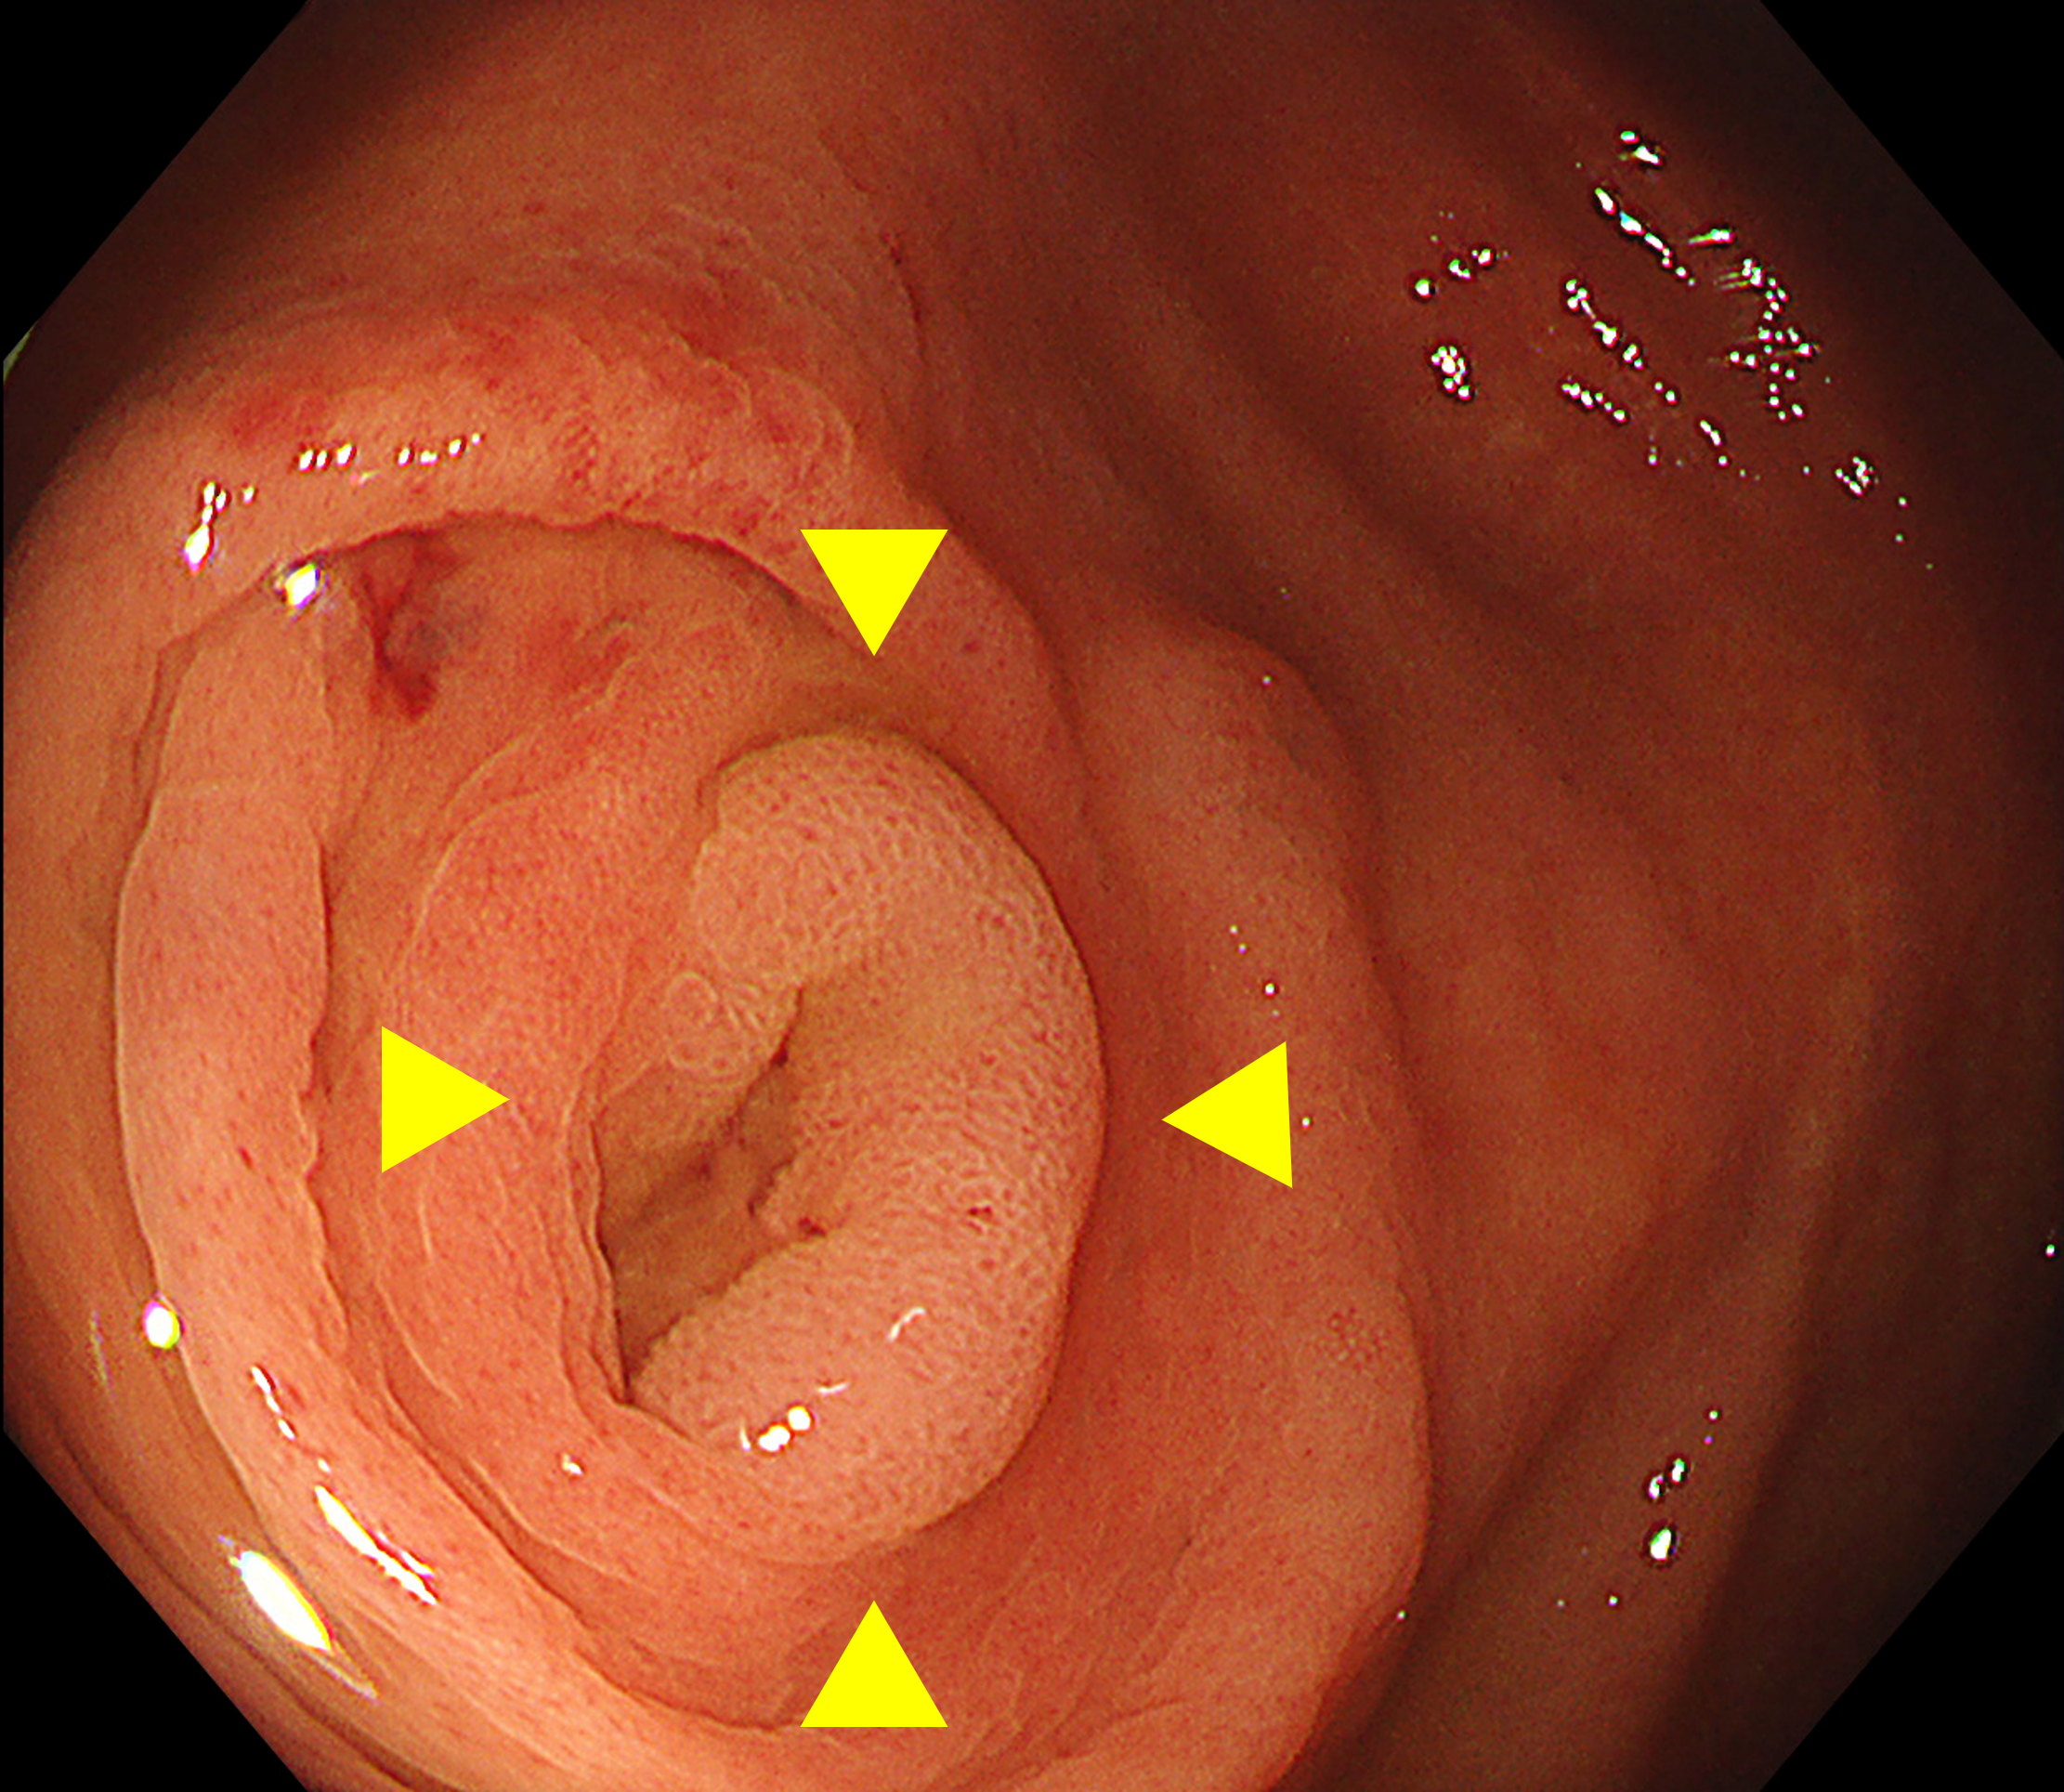

盲腸では、虫垂開口部周囲や回盲弁の裏側が死角となりやすい(※Figure1)。盲腸底部から全体を俯瞰するように観察し、回盲弁は唇裂部を意識して十分に送気・近接観察を行うことが重要である(※Figure2)。

• ※Figure 1. 虫垂口に入り込む病変